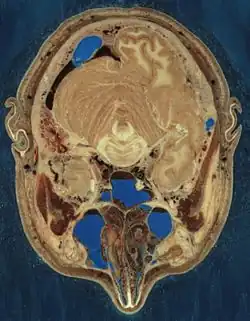

With computed axial tomography, computers construct cross-sections from x-ray data.

Cryosection of a human head

Cryosection of a human head